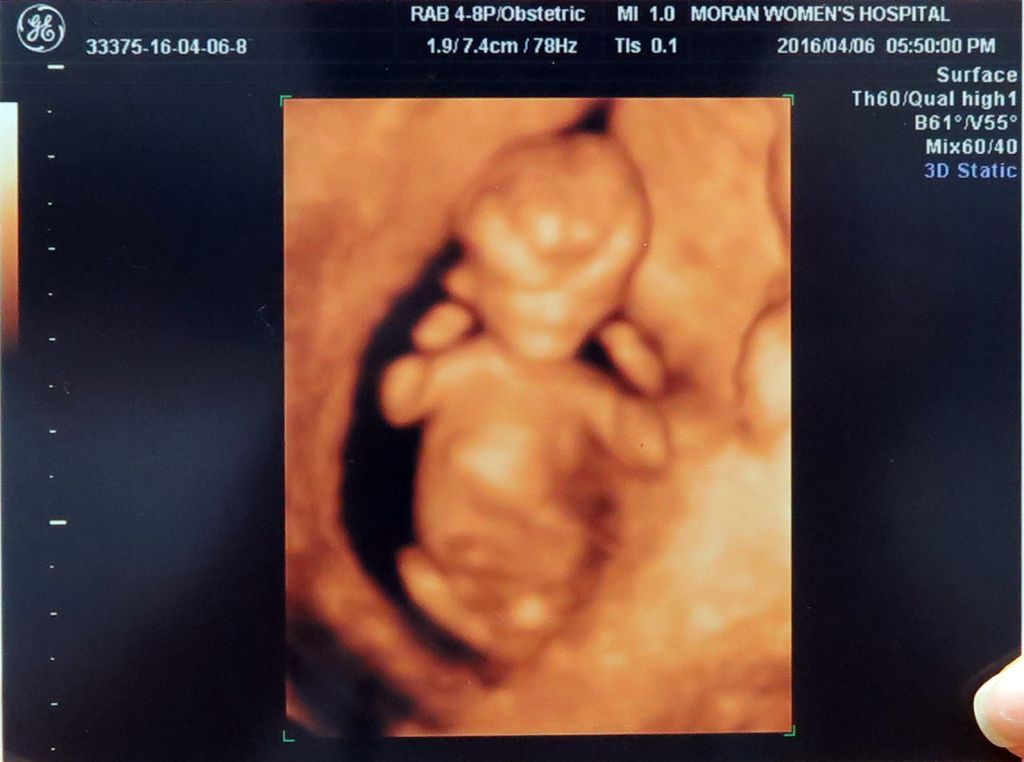

별이 12주~★

2016-04-06

한달만에 별이 보러 병원에 다녀왔습니다. 별이는 별탈 없이 잘크고 있다네요. 입체 초음파로 보니 아빠가 되었다는 사실이 더 와닿습니다. 크기는 5.7cm로 12주 아가에 딱 맞게 크고 있고 심장도 아주 튼튼하게 뛰고 있어요. 초음파 초기에 아주 역동적으로 움직이더니 검사할때 아주 얌전하게 있었어요. 우리 별이 모습을 확인하시려면 아래 동영상 플레이~~^^ BGM은 악동뮤지션의 <작은별> 입니다. 우리Read More →